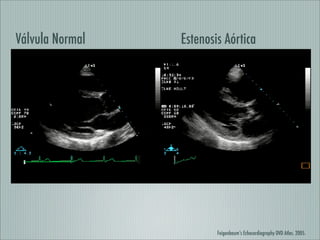

Este documento resume la cardiopatía reumática, incluyendo su epidemiología, manifestaciones clínicas, diagnóstico, tratamiento agudo y crónico. Explica las complicaciones valvulares como la estenosis y la insuficiencia mitral y aórtica, así como su manejo médico e intervencionista. En resumen, provee una descripción completa de esta enfermedad cardíaca asociada a fiebre reumática.